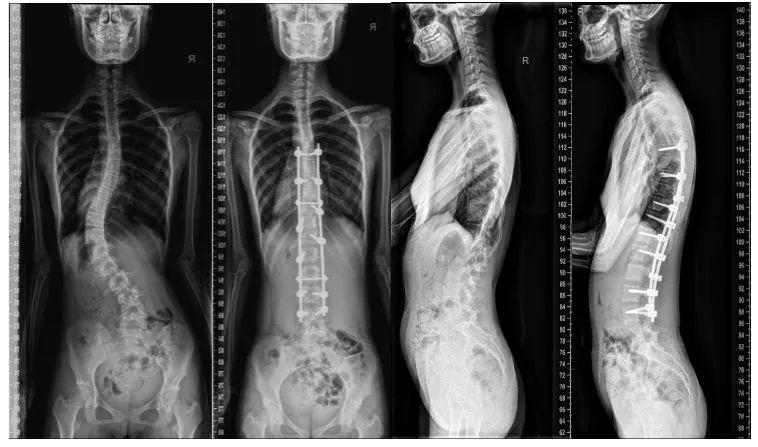

正常脊柱侧位片,全脊柱正侧位片

全脊柱正侧位片

全脊柱正侧位片图片

脊柱侧弯